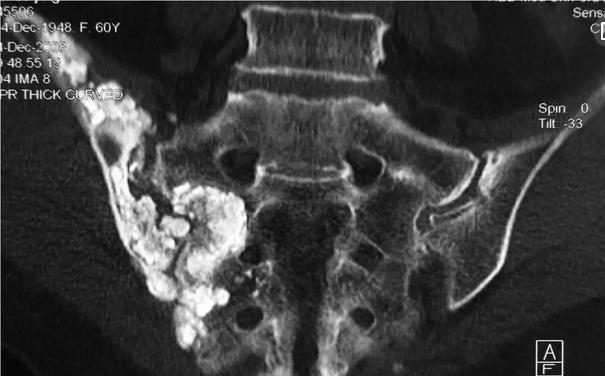

骨结核疾病是全身疾病体现在局部的表现,骨结核对患者的身体危害是非常严重的,除了对骨质的的破坏还会对患者的肌肉产生很大的危害,那么骨结核会造成肌肉萎缩吗?>>>不想看文章,可直接在线咨询

我院的骨结核专科医生介绍,骨结核患者的肌肉萎缩初是由于神经性营养障碍,而后会与肢体的无用有关,先是肌肉紧张力比健康时减弱,肌力减弱后肌肉会萎缩无力,此外,患肢尤其是患病关节周围的皮下脂肪层增厚,出现肌肉萎缩状态>>>我已经出现肌肉萎缩还有救吗?

针对骨结核患者的情况,我院一般采取中医保守治疗。纯中医的“靶位定向体液疗法”在治疗骨结核上,主要是”靶位“给予治疗,通过改变结核杆菌赖以生存的环境,使结核杆菌自然死亡,在不干扰和破坏正常人体机能条件下,整体带动局部,恢复局部的生理体液循环,实现骨结核疾病的治疗好。在患者没有瘫痪的前提下,治疗好后的功能活动逐渐让患者的患肢重新恢复以往的状态。>>>我适合此疗法吗?